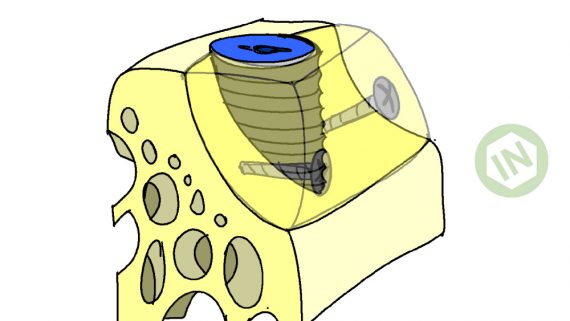

Обратите внимание на то, что мы не погружаем имплантаты слишком глубоко. Полированная фаска имплантата должна находиться выше уровня костной ткани.

Чрезмерное погружение имплантов — одна из наиболее распространенных ошибок в имплантологии, грозным осложнением которой является периимплантит и рецессия десны в области соседних зубов. С этой точки зрения, лучше недокрутить, чем перекрутить.

Я планирую установить имплантат Friadent Xive диаметром 4,5 мм, что максимально соответствует размеру зубов пациента. Обратите на положение аналога абатмента по отношению к соседней четверке. Это очень важный момент.

Также обратите внимание, что я не погружаю импланты слишком глубоко — только до края полированной фаски.